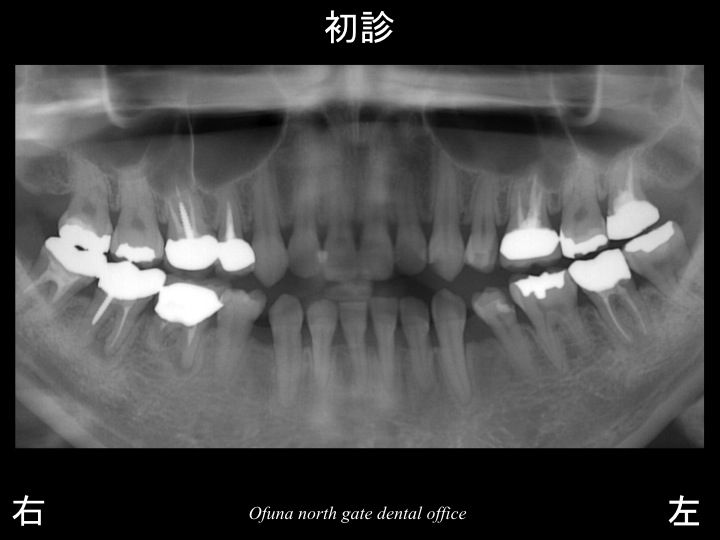

まず1症例目になります。

以下が初診時です。

上顎前歯部の被せ物が取れて、他歯科医院で診断してもらったところ

歯根破折 を起こしており、抜歯しか方法がないと言われ、なにか方法はないかと考え、当医院を受診した方です。

当医院でもレントゲン等の診査を行った結果、

最初に受診した歯科医院と同様の診断で、

歯根破折 でした。

この歯根破折 した歯は抜歯になります。

抜歯しか方法がないのです。

ここで一番考えなければいけないのが、

歯根破折 した原因です。

神経がないからは本当にトラブルが多いです。

ここで この患者様の口腔内全体を見てみましょう!

以下のレントゲン写真の赤丸は神経がない歯です。

ほとんどの歯が神経がありません。

今後が本当に心配な方です。